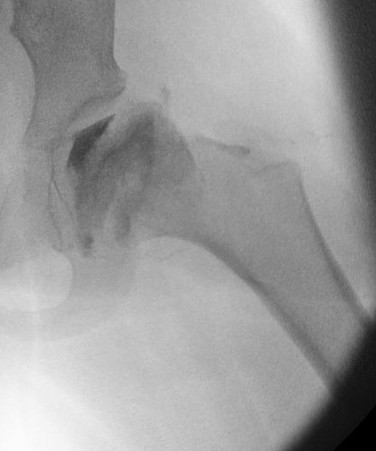

Hinge abduction

- move medial, better-preserved part of the femoral head into the loading zone

- reduce adduction contracture and distalize the greater trochanter